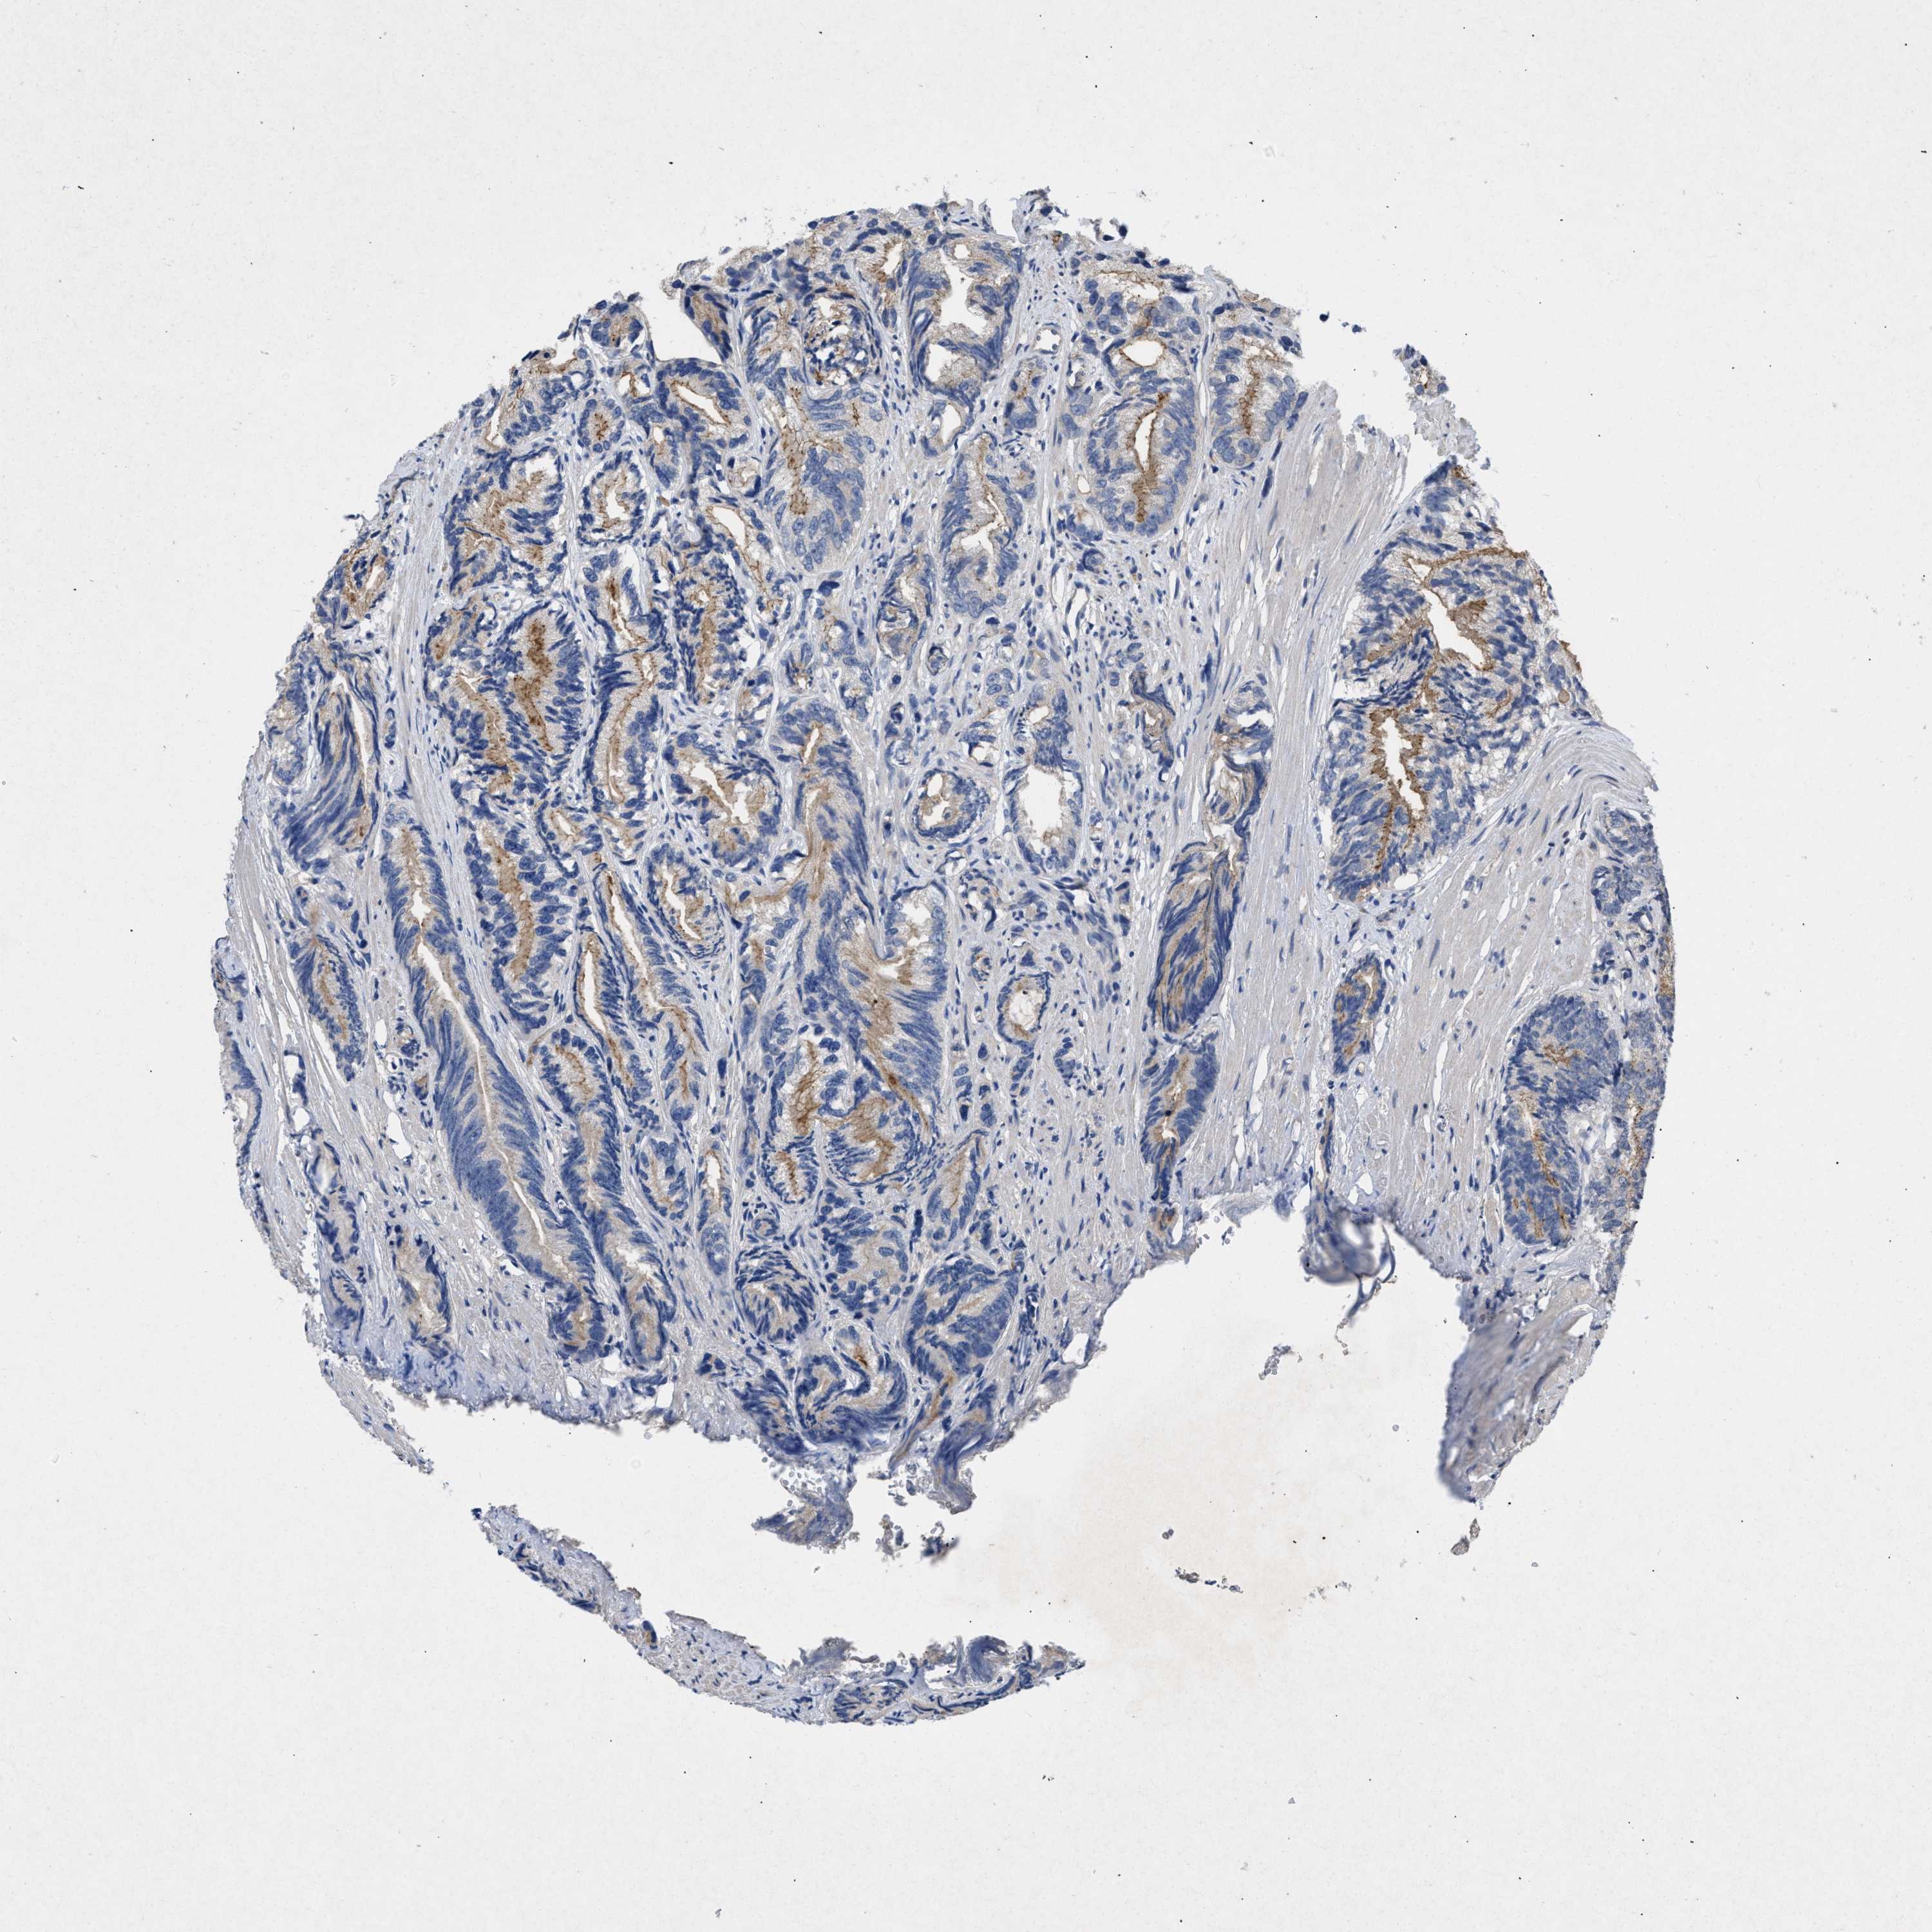

PROSTATE CANCER - Protein expressioni

A mouse-over function shows sample information and annotation data. Click on an image to view it in a full screen mode. Samples can be filtered based on level of antibody staining by selecting one or several of the following categories: high, medium, low and not detected. The assay and annotation is described here.

Note that samples used for immunohistochemistry by the Human Protein Atlas do not correspond to samples in the TCGA dataset.

Antibody stainingi

Antibody staining in the annotated cell types in the current human tissue is reported as not detected, low, medium, or high, based on conventional immunohistochemistry profiling in selected tissues. This score is based on the combination of the staining intensity and fraction of stained cells.

Each image is clickable and will lead to virtual microscopy that enables deeper exploration of all samples and also displays staining intensity scores, fraction scores and subcellular localization as well as patient and tissue information for each sample.

Antibody CAB018751

Antibody CAB034411

Staining

High

Medium

Low

Not detected

Intensity

Strong

Moderate

Weak

Negative

Quantity

>75%

75%-25%

<25%

None

Location

Nuclear

Cytoplasmic/membranous

Cytoplasmic/membranous,nuclear

Adenocarcinoma, High grade

Adenocarcinoma, Low grade